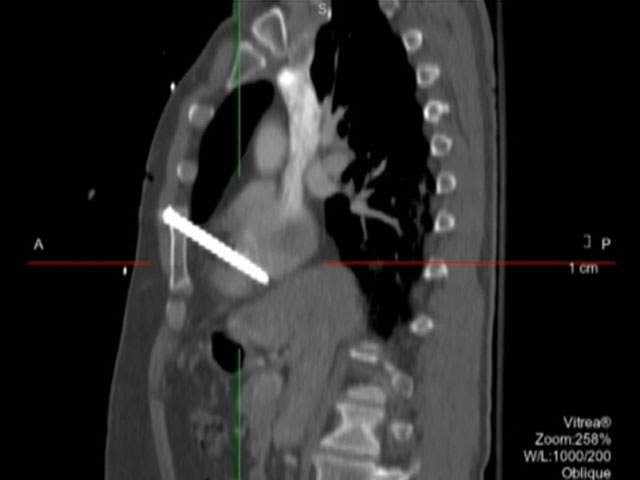

A Minnesota carpenter received much more than a splinter while building a deck at his neighbor’s home. Eugene Rakow was using a nail gun to drive 3.5-inch nails when the tool bounced back, hit his chest and fired one of the nails deep inside his heart, missing an artery by two millimeters. He was able to get to his truck and call his wife for help. Rakow underwent open heart surgery to remove the nail and is expected to make a full recovery.